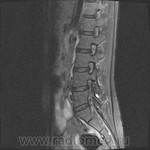

Пациентка 25 лет обратилась к неврологу с жалобами на слабость, изменение походки. Раньше не обследовалась.

Я специально сделал изображения потемнее, чтобы выделить патологию (жировую дегенерацию) именно мышечной ткани.

В заключении я предположил болезнь Штейнерта. Хотелось бы выслушать мысли коллег.

Евгений, пожалуйста, поподробнее для начинающих. Что и где нашли, ткните пальцем.

Гм, как это я пропустил эту публикацию. Поясничные мышцы замещены жировой тканью; т.е. Они выглядят "белыми" на Т1 и Т2, в последовательности с подавлением жира, соответственно сигнал уходит; и они "тёмные". Такую картину я видел у пожилых, иногда у пациентов после операции на позвоночнике. По поводу болезни Штейнерта, должна быть клиника, изменения и гипотония/атония мышц других локализаций. На основании только МРТ ПОП не совсем убедительно. Вот небольшая ознакомительная статейка.